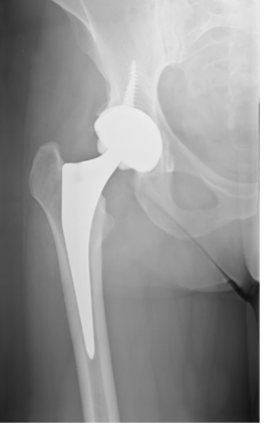

Quando outros tratamentos não são suficientemente eficazes, algumas pessoas com artrose recorrem à cirurgia. Por exemplo, algumas pessoas passam por uma cirurgia para substituir um quadril ou joelho (como na figura abaixo).

Estas cirurgias geralmente têm bons resultados quando indicadas no momento adequado, melhorando a dor e a função. O médico que faz este tipo de tratamento é o ortopedista.